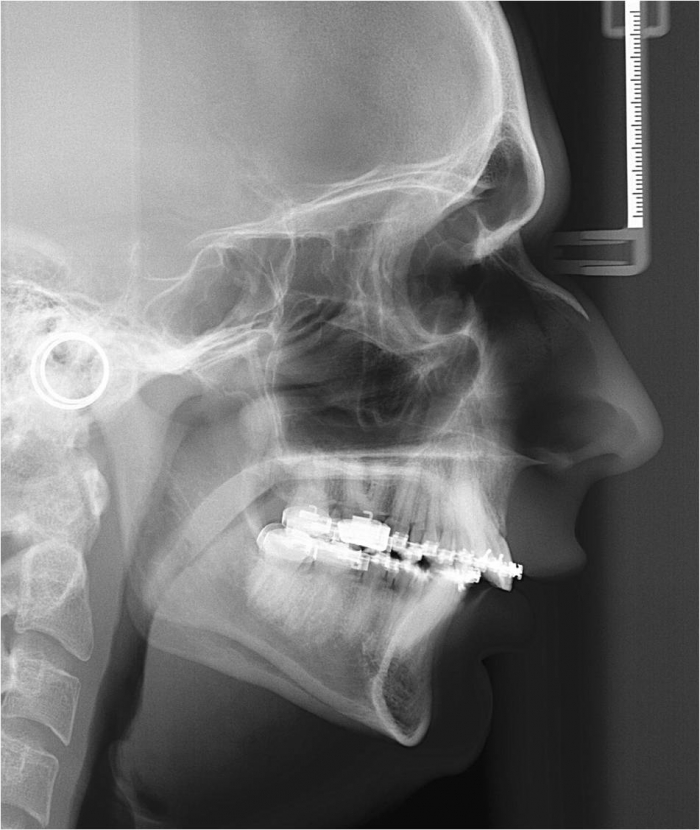

Telerradiografia inicial

Telerradiografia após a cirurgia